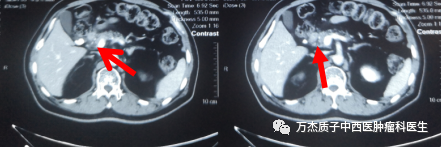

放疗同时口服“替吉奥胶囊”60mg bid d1-14 q21d同步化疗。放疗期间复查上腹部CT提示胰腺颈部病灶明显缩小,胰头部低密度灶较前相仿,腹腔淋巴结较前缩小,综合评效为疾病稳定,按原计划加量2次,总剂量:54cGE/2.0cGE/27f。患者治疗期间以及治疗后无不良反应发生。

下图为质子治疗前肿瘤病灶显示情况,箭头所指处为胰腺肿瘤病灶

下图为质子治疗后半年复查的影像,显示肿瘤病灶缩小明显